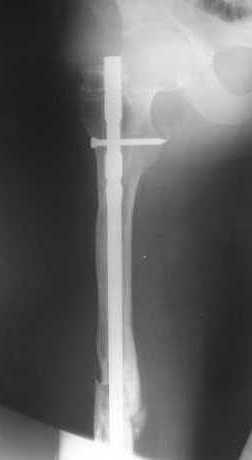

В приложении пример, как их использовали после остеотомии бедра по поводу сросшегося с вальгусом перелома, чтобы не дать гвоздю уйти во внутренний мыщелок.

Пациенту М., 30-ти лет, 1,5 года назад в одной из московских больниц был выполнен остеосинтез бедренной кости штифтом UFN (диаметр штифта 9 мм).

К нам больной поступил с признаками ложного сустава бедренной кости, перелома

штифта и дистального блокирующего винта (images 1,2,3).